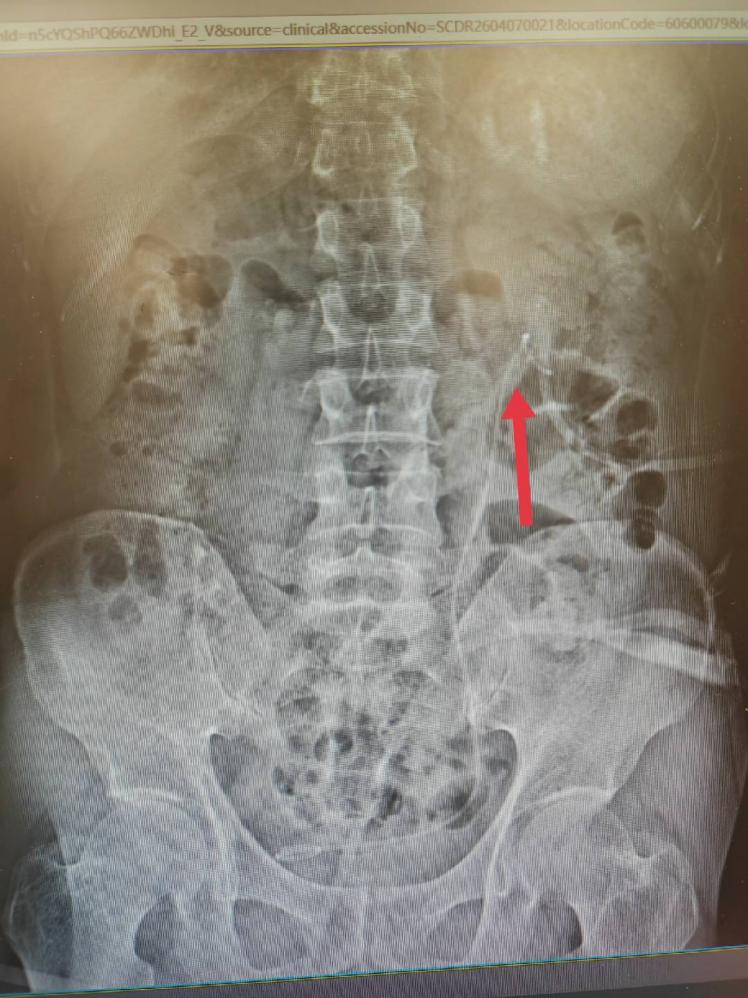

术后腹部平片:

该患者结石经成分分析确诊为「一水草酸钙结石」,为后续个性化防复发治疗提供了精准依据,也充分彰显了我科「泌尿系结石一体化综合治疗」的独特优势。我科建立了从精准诊断、微创治疗、结石分析到防复发管理的全程闭环诊疗体系,针对不同成分、不同部位的结石制定个体化方案,真正实现「治已病、防未病」。